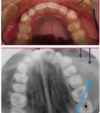

Is this Globulomaxillary Cyst , lateral granuloma or OKC?

~ it is kind of a teardrop or pear shaped size

~Little less well differentiated in this particular instance but again unilocular radiolucency between the roots of two teeth

This one ended up being an OKC